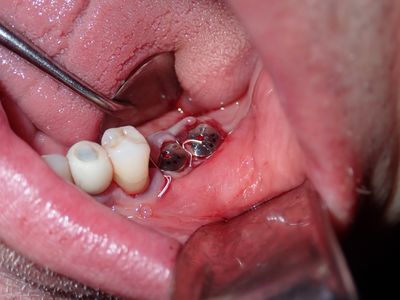

large amount of bone loss at time of exo 36/37 done 2 months ago. Good healing of bone except for small socket area at 36 region. buccal bone lower than palatal about 1mm, decided to place tissue level implants opposed to grafting, gaining back height is unlikely, difficult access case with large tongue. Implants placed with 36 about 1.5mm buccal exposed, 37, .5mm mesial exposed, healing abutments palced grafted all sites with sticky bone followed by collagen membrane soaked in prf fluid, 2 holes cut for implants. additonal fibrin membrance placed on buccal prior to suturing.